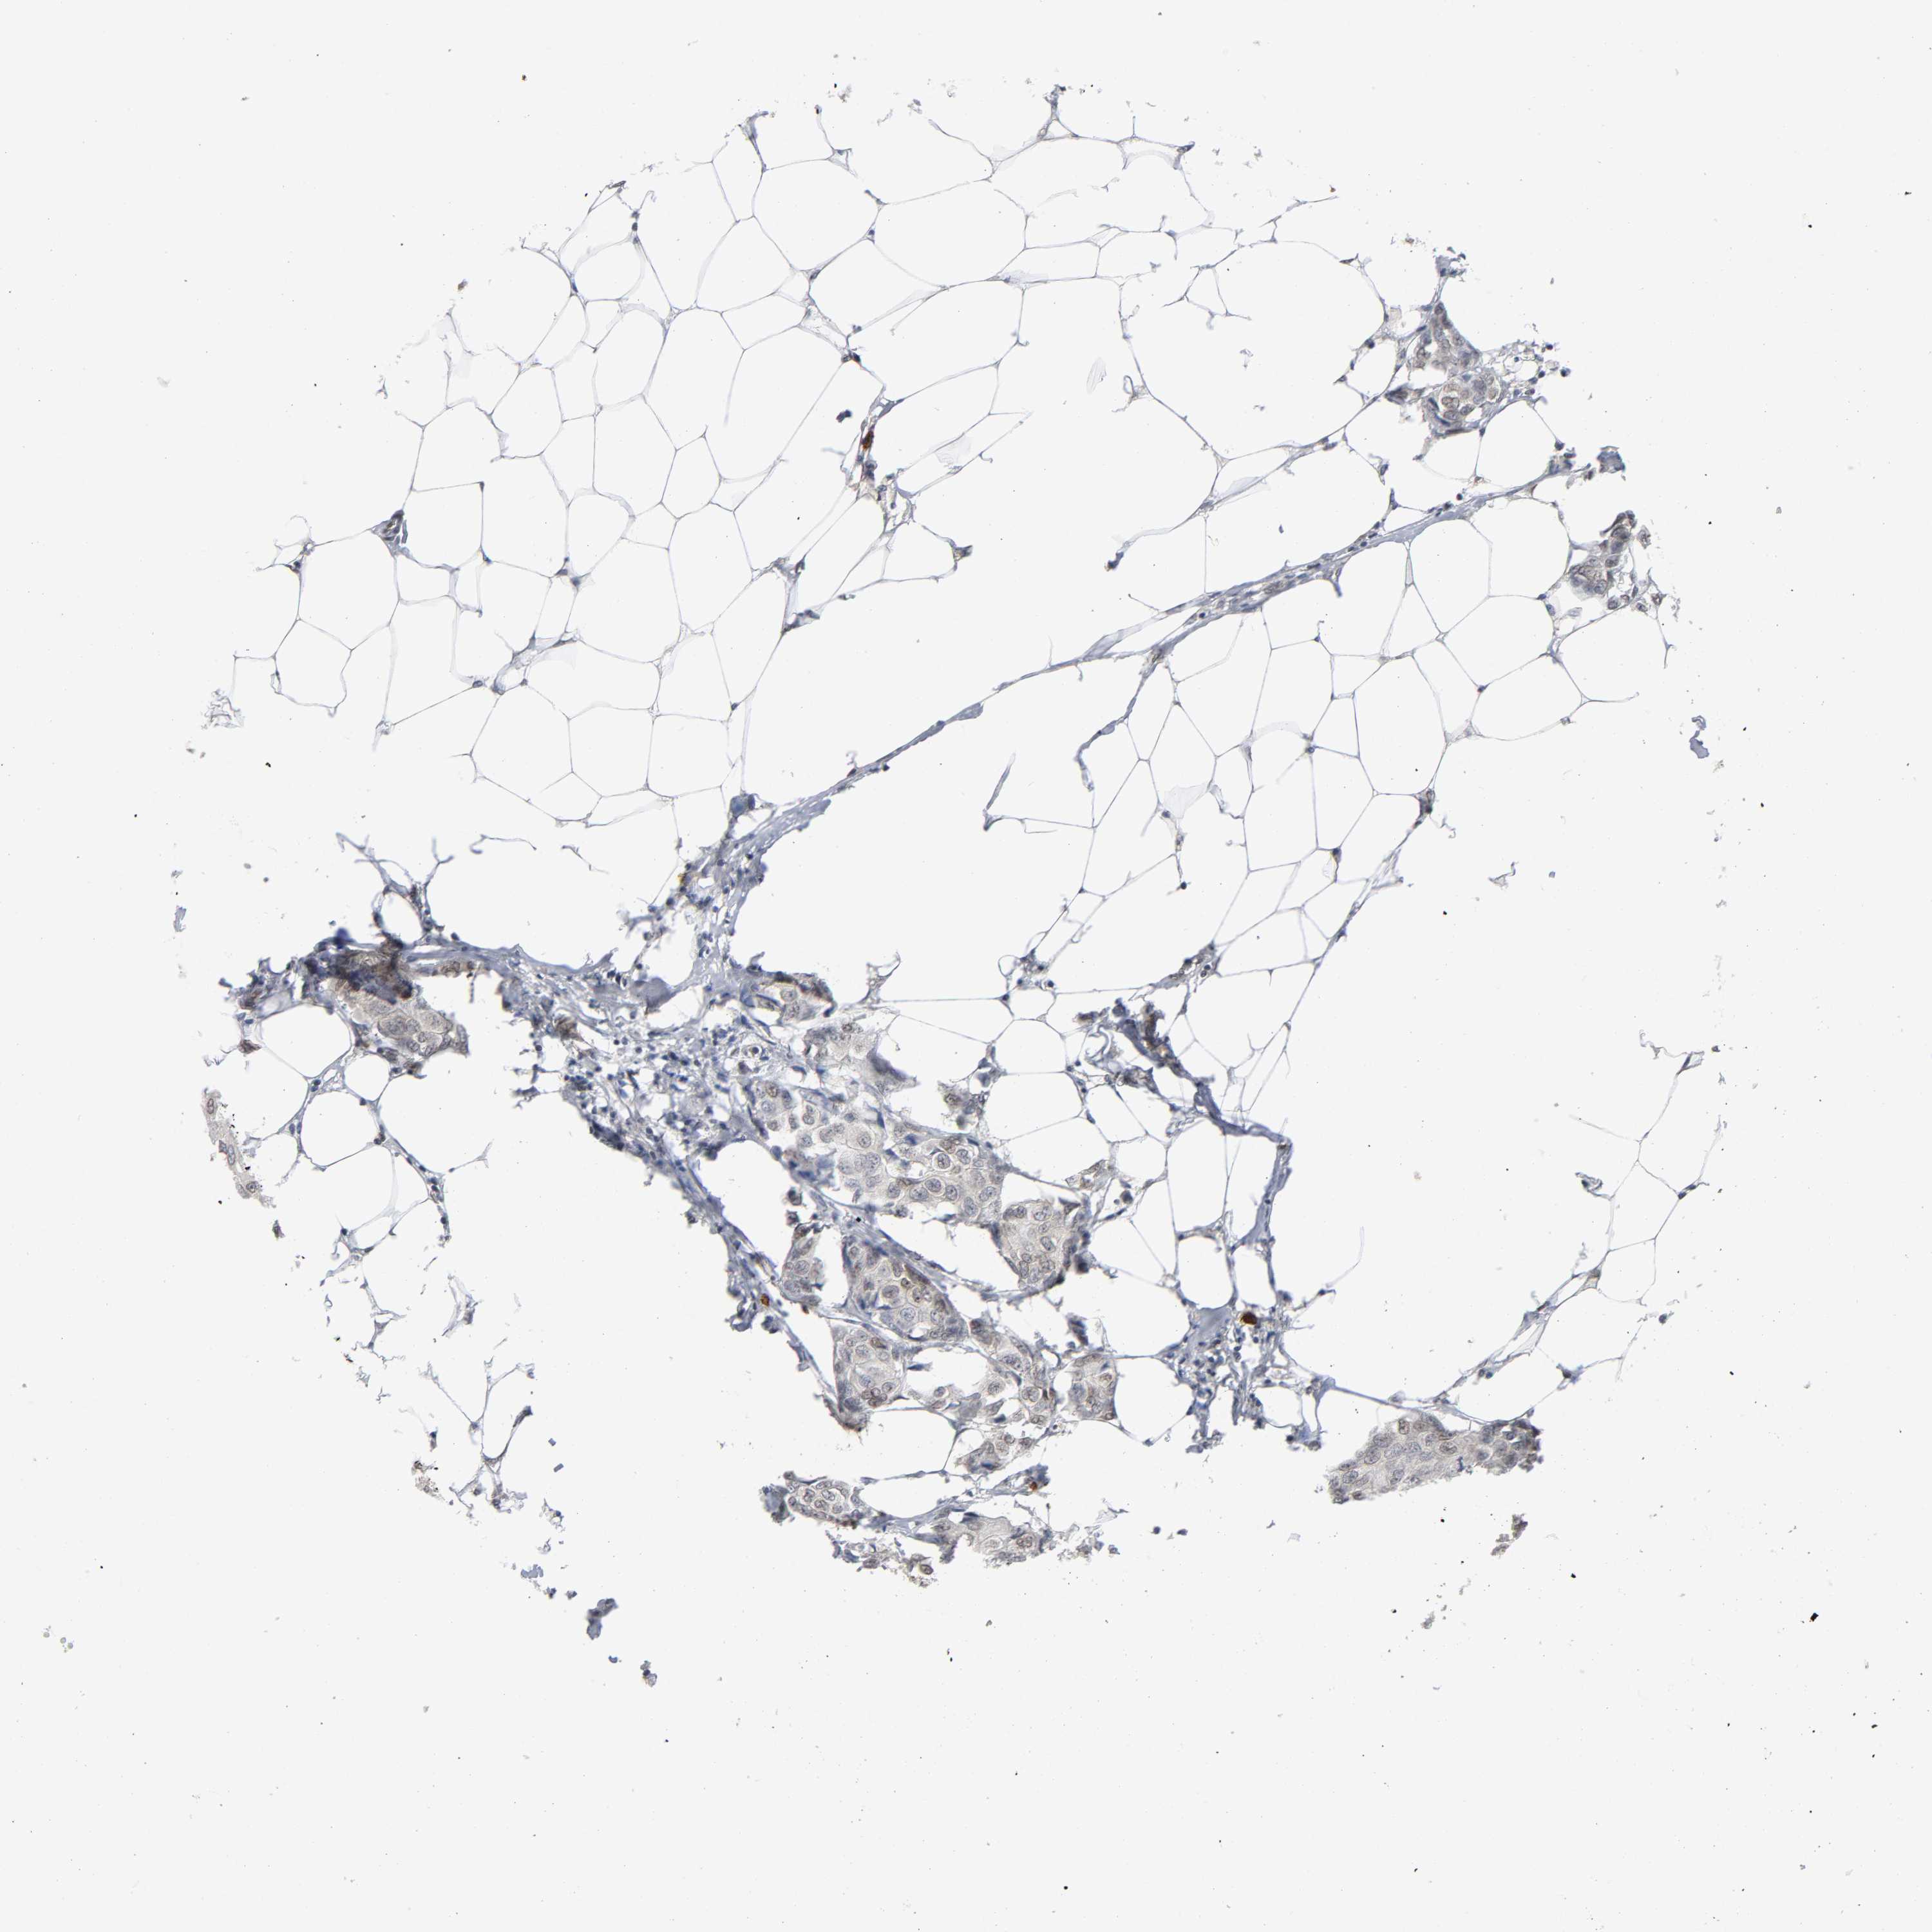

Breast cancer

Human cancer